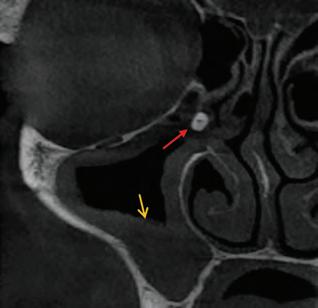

93 CLINICAL TIPS CBCT for general practitioners

IDA delegation meets with Minister